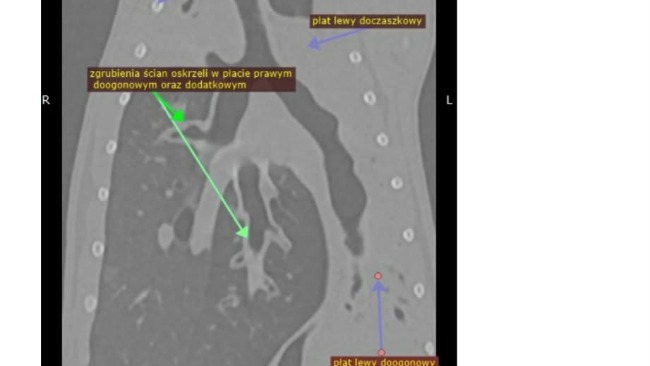

Jak już wiecie nasza mała koteczka Pieczarka czyli Kicisława ma cały czas problemy zdrowotne, nadal nie wiemy co jest ich przyczyną i staramy się robić wszystko aby miała szanse na normalne, długie i szczęśliwie życie.

Wykonalismy tomografię, posiewy, bdania krwi, usg kontrolne, a ostatnio miała punkcję osierdzia iściągnięcie płyku, którego jeszcze tydzień temu nie było, teraz czekamy na wyniki, może wreszcie dowiemy z czym ona i my walczymy.